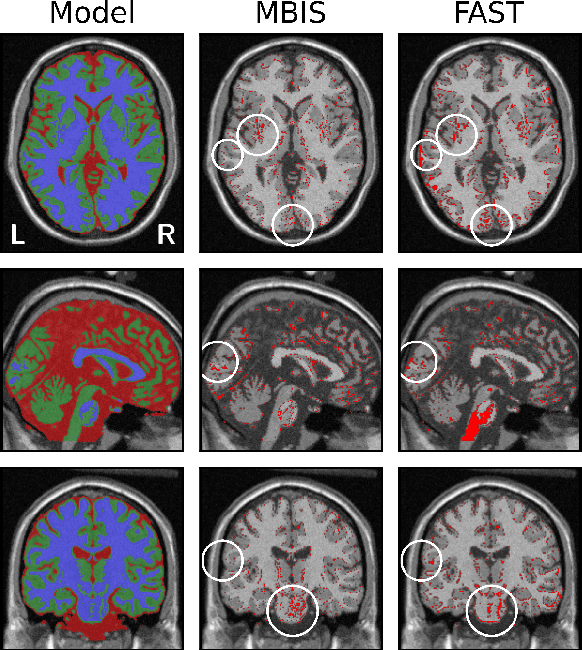

Abstract:We present MBIS (Multivariate Bayesian Image Segmentation tool), a clustering tool based on the mixture of multivariate normal distributions model. MBIS supports multi-channel bias field correction based on a B-spline model. A second methodological novelty is the inclusion of graph-cuts optimization for the stationary anisotropic hidden Markov random field model. Along with MBIS, we release an evaluation framework that contains three different experiments on multi-site data. We first validate the accuracy of segmentation and the estimated bias field for each channel. MBIS outperforms a widely used segmentation tool in a cross-comparison evaluation. The second experiment demonstrates the robustness of results on atlas-free segmentation of two image sets from scan-rescan protocols on 21 healthy subjects. Multivariate segmentation is more replicable than the monospectral counterpart on T1-weighted images. Finally, we provide a third experiment to illustrate how MBIS can be used in a large-scale study of tissue volume change with increasing age in 584 healthy subjects. This last result is meaningful as multivariate segmentation performs robustly without the need for prior knowledge